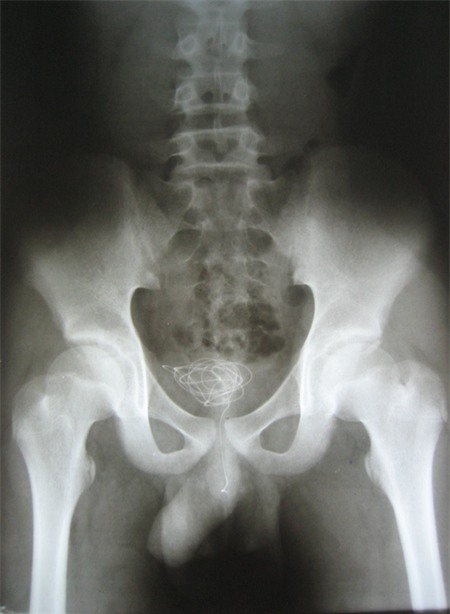

Sợi dây điện nằm gọn trong bàng quang của trẻ

P. nhập viện trong tình trạng đau bụng dưới dữ dội. P. nói với bác sĩ, hai ngày trước khi nhập viện đã có hiện tượng đau bụng như vậy nhưng vì xấu hổ nên em không dám nói với gia đình. Bởi lẽ, P. đã nghịch dại, tự mình nhét nguyên sợi dây điện vào “cậu bé” của mình.

Xét nghiệm hình ảnh, các bác sĩ thấy cả sợi dây nằm gọn trong bàng quang của P., với một đầu còn nằm lửng lơ trong niệu đạo. Khi “vật chứng” được lấy ra ngoài, các bác sĩ đều ngạc nhiên vì sợi dây điện dài đến 1 m, đường kính khoảng 3 mm, lõi đồng còn bọc nhựa.

Dị vật được lấy ra khỏi bàng quan của P.

Theo bác sĩ, đây là trường hợp may mắn vì hai đầu lõi đồng của sợi dây điện không lộ ra nếu không đã có thể gây rách niệu đạo, bàng quang của P. Phần may mắn tiếp theo là sợi dây dài như thế mà không tạo nút thắt nên bác sĩ có thể nội soi gắp dị vật qua đường tự nhiên, chứ không cần mổ mở ổ bụng.

“Trường hợp này, nếu không được kịp thời xử lý, dị vật có thể tiếp tục di chuyển, bị lạc trong cơ thể, gây nhiễm trùng bàng quang, niệu đạo, đặc biệt là nhiễm trùng thận. Khi thận bị tổn thương thì sẽ gây hậu quả lớn, ảnh hưởng đến chức năng sinh lý sau này”, bác sĩ Thạch đánh giá.